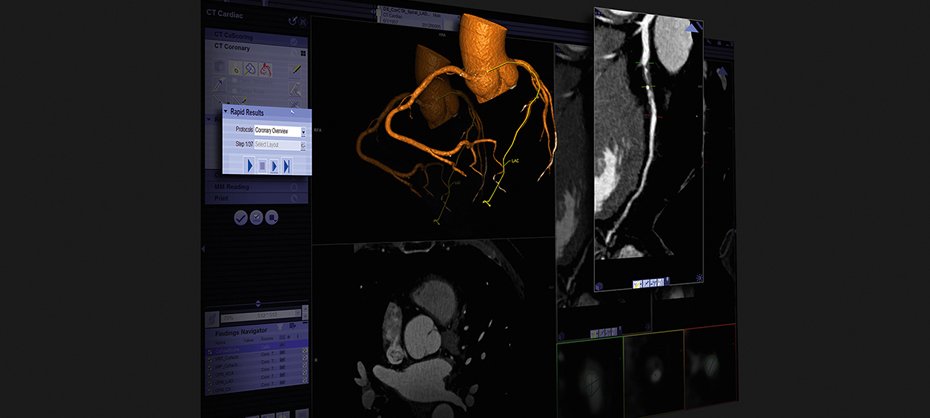

Sky Teleradiology is dedicated to provide excellence in diagnostic Teleradiology interpretations and consultative services across the india. Sky tele provides complete 24 x 7 teleradiology reporting coverage for diagnostic image interpretations for conventional radiology (CR/DR), ultrasound, color Doppler, CT scan, MRI,etc. We also offer preliminary and final interpretations to those hospitals and diagnostic centers that need some extra support either for overflow during busy hours, vacation coverage or weekends.

We partner with diagnostic centers, hospitals, medical groups and other entities requiring remote, off-site reading of diagnostic imaging studies by using our Teleradiology services. We have the state-of-the-art infrastructure and expertise available to provide round-the-clock, reliable, and efficient service to our clients.